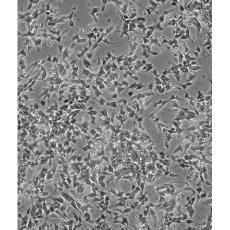

產品名稱 SH-SY5Y [SHSY-5Y]

中文名稱 人神經母細胞瘤細胞

組織來源 神經母細胞瘤;骨髓來源;男性

生長特性 mixed, adherent and suspension

形態特征 epithelial-like and neuronal-like

細胞描述 SH-SY5Y cells have a reported saturation density greater than 1×10^6 cells/cm^2. They are reported to exhibit moderate levels of dopamine beta hydroxylase activity. Ref